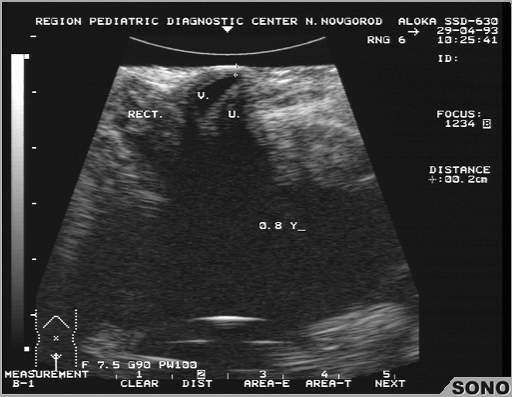

Маточная беременность